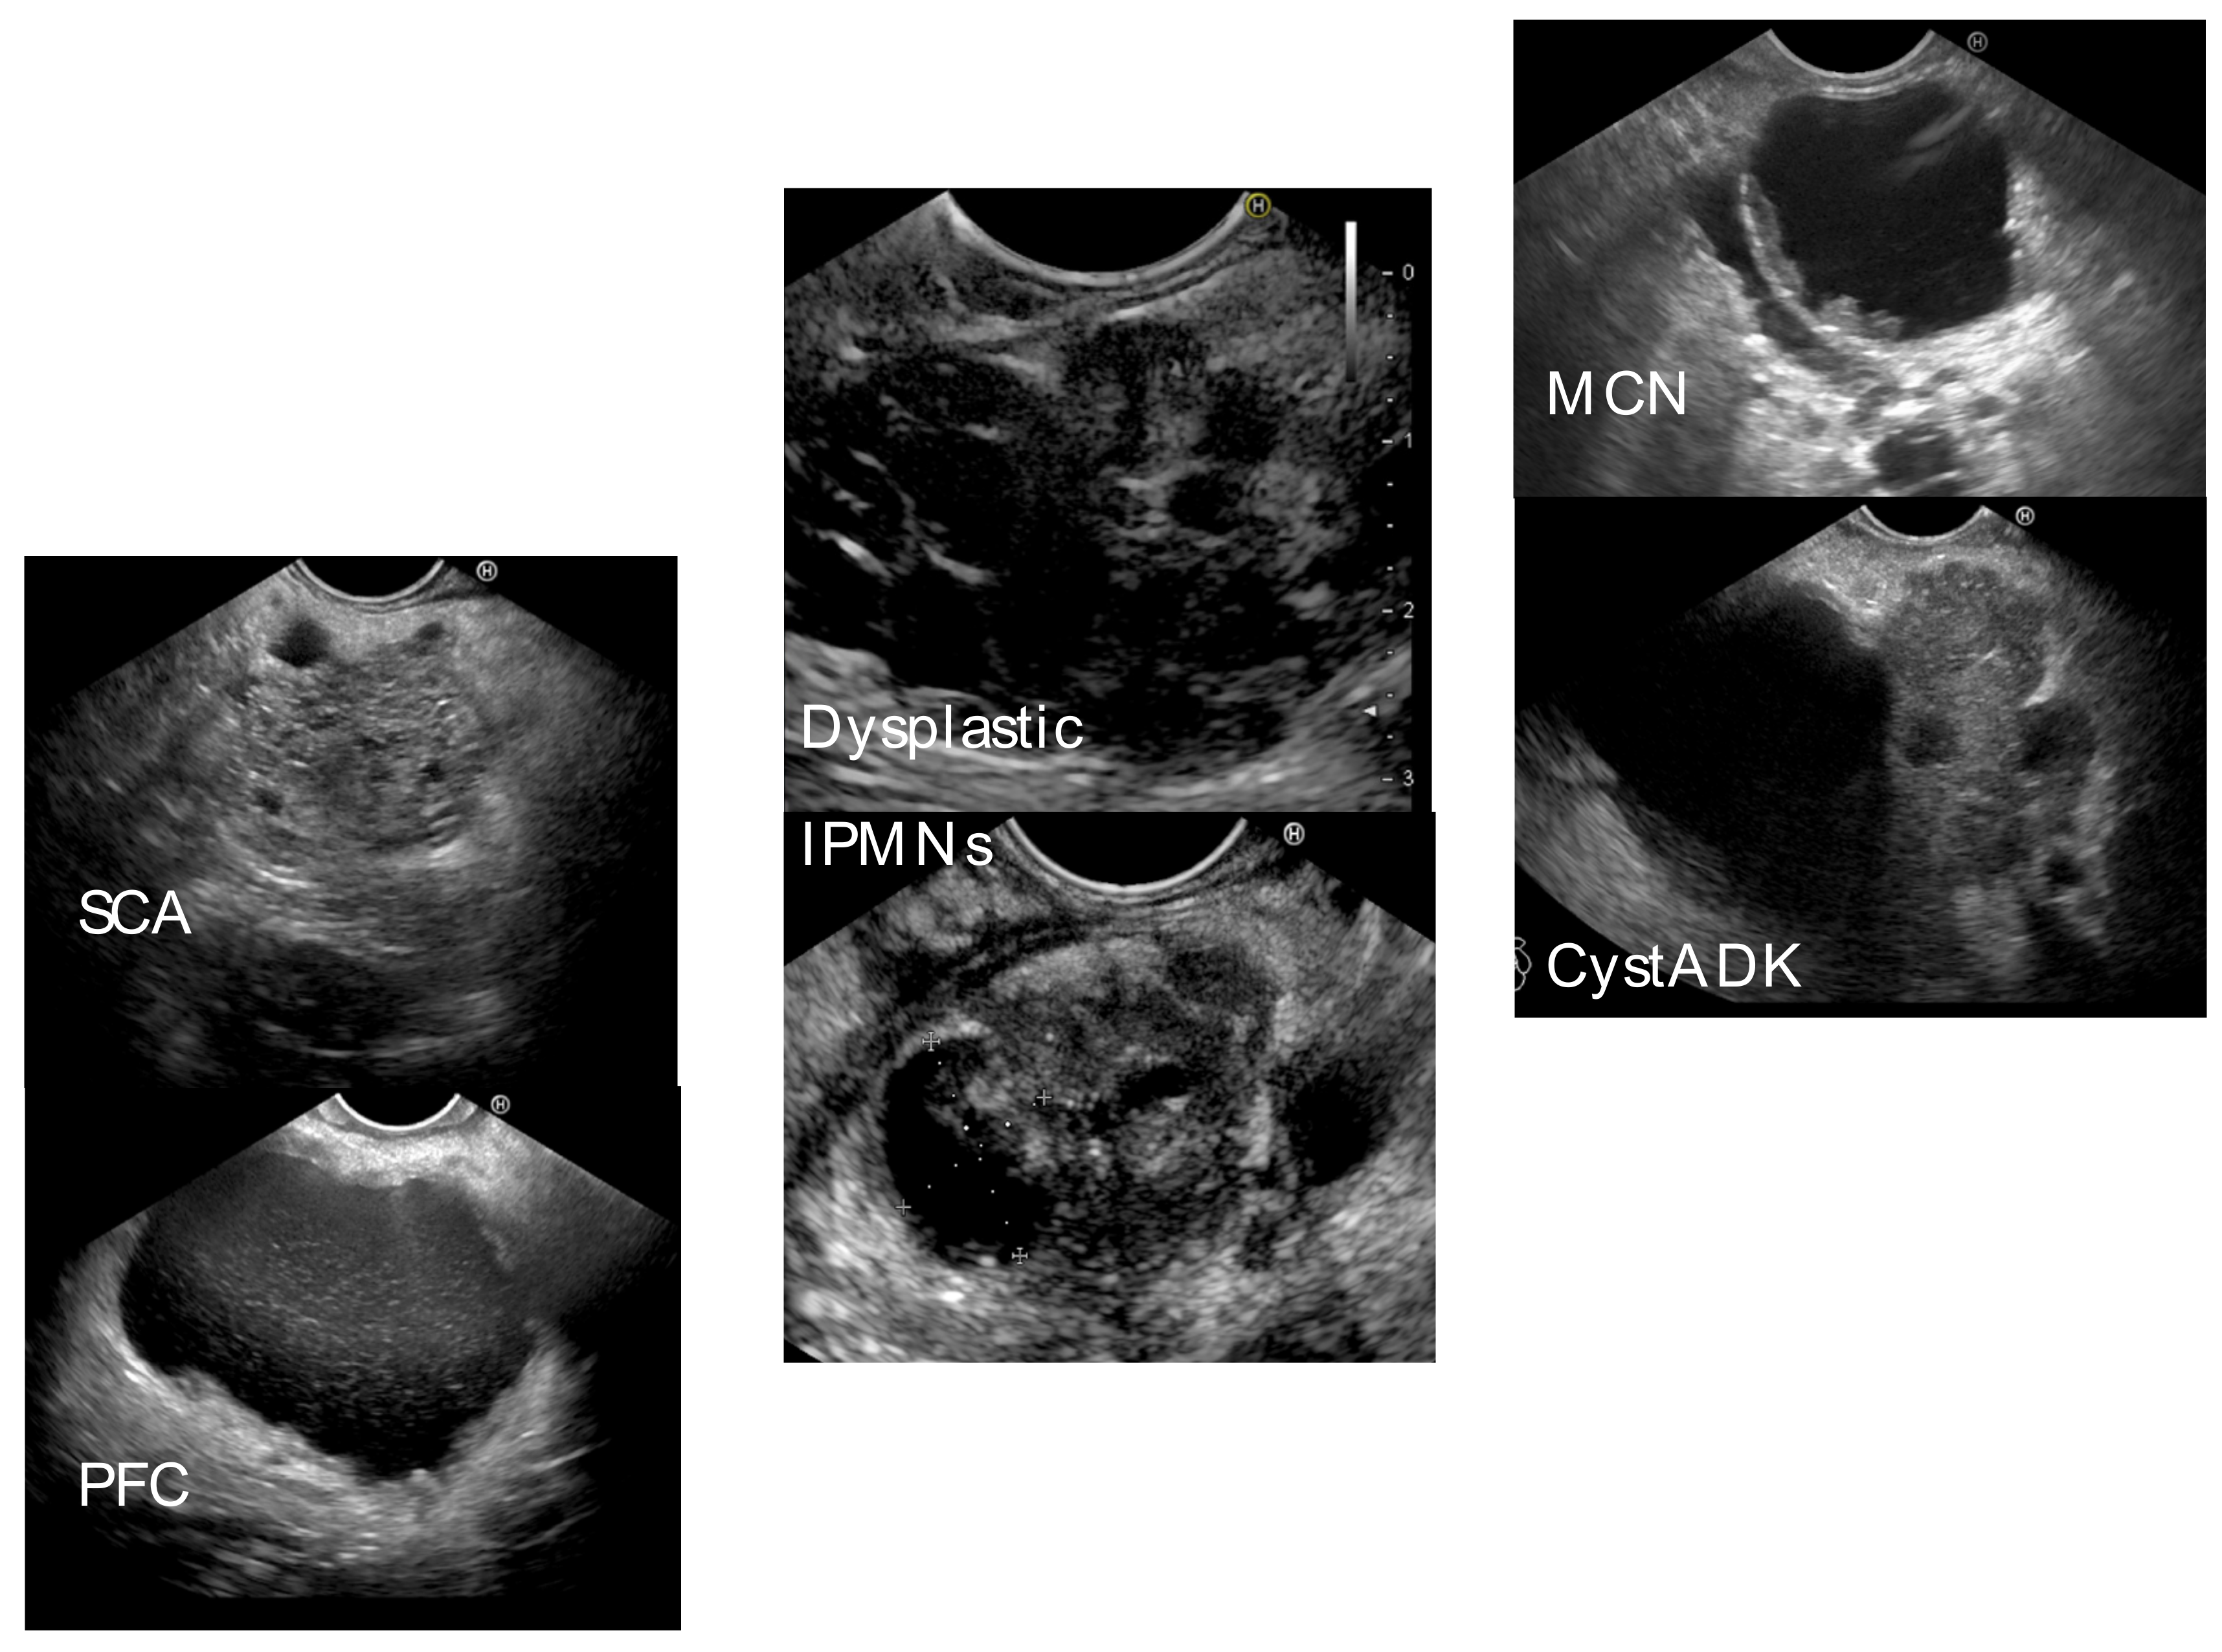

| Type of cystic lesion | |

| Pseudocyst | 25 (30.9) |

| WON | 2 (2.5) |

| IPMN (total) | 35 (43.2) |

| MD-IPMN | 9 |

| SB-IPMN | 25 |

| Mixed-IPMN | 1 |

| MCN | 9 (11.1) |

| Cystadenocarcinoma | 4 (4.9) |

| SCA | 5 (6.2) |

| NET | 1 (1.2) |